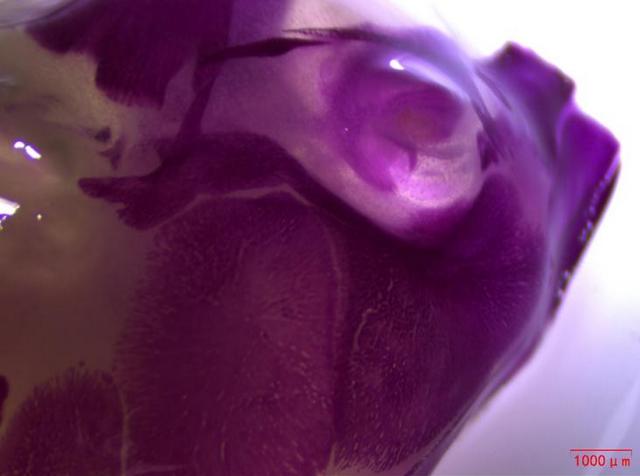

近日,湖南某生物企業(yè)引進(jìn)了Mshot明美生產(chǎn)的體視顯微鏡MZ101,用于觀察小動物大體組織,如小鼠幼崽的脊柱和頭部。體視顯微鏡MZ101以成像清晰、超長工作距離和大視野目鏡等顯著特點(diǎn),為生物企業(yè)的科研人員提供了良好的觀察體驗(yàn)。

在動物實(shí)驗(yàn)研究領(lǐng)域,對小動物大體組織的清晰觀察至關(guān)重要。明美體視顯微鏡MZ101憑借其高分辨率和優(yōu)異的光學(xué)性能,能夠捕捉到小鼠幼崽脊柱和頭部的每一個細(xì)節(jié),成像效果令人贊嘆。這無疑為科研人員提供了準(zhǔn)確、可靠的數(shù)據(jù)支持,有助于推動藥物研發(fā)進(jìn)程的順利進(jìn)行。